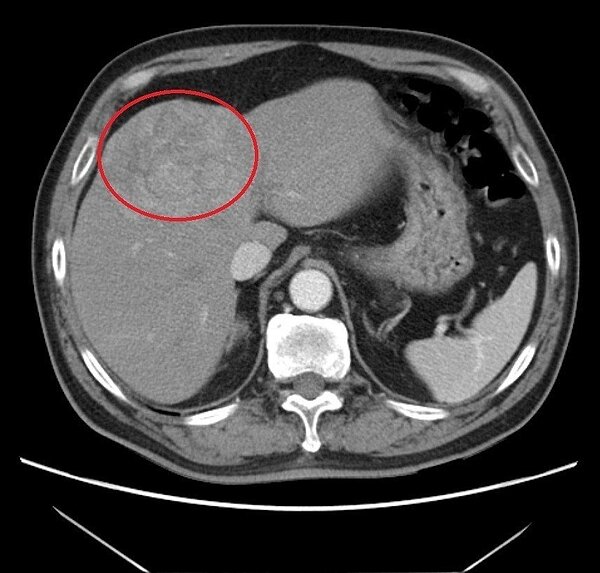

王姓病患因指數異常進一步檢查,發現一顆大於7公分的肝臟腫瘤(紅圈處)。圖/大千綜合醫院提供

苗栗縣60歲王姓男子平日不菸不酒,但體檢時發現「胎兒蛋白」數值高於標準值,到醫院進一步檢查發現他的肝臟有顆大於7公分的腫瘤,醫師詢問病史,他不知自身是B型肝炎帶原者,病患在醫師的建議下接受第一次肝臟局部栓塞治療,讓腫瘤縮小,再搭配B型肝炎治療,目前控制穩定,胎兒蛋白指數也明顯下降,在門診定期追蹤治療。